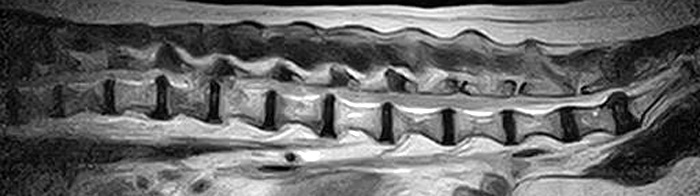

市内の先生からダックスちゃん両後肢麻痺グレード5でMRI検査及び手術依頼でご紹介がありました。MRI検査で第13胸椎-第1腰椎間椎間板ヘルニア、右側優位な圧迫と診断し手術となりました。→<その2>へ続く